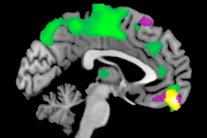

تمكن علماء من جامعة بوسطن من بناء خريطة مذهلة للدماغ بواسطة تقنية ثلاثية الأبعاد، والتي تبين الخلايا العصبية الفردية بتفاصيل غير مسبوقة.

تم إنشاء الخريطة من خلال سلسلة من الصور التي التقطت بطريقة تسمح بالتصوير وفقا للمقياس النانوي، أو واحد في المليون من المليمتر.

يشار إلى أن تقنيات تصوير الدماغ التقليدية، بما في ذلك التصوير بالرنين المغناطيسي، يمكنها فقط الوصول الى الميزات التي تصل إلى حوالي ملليمتر. أما نظام التصوير الجديد، فهو يعتمد على أحدث الأجهزة التي تمكّنه من الوصول الى عينات الدماغ، وهو حائز على براءة اختراع.